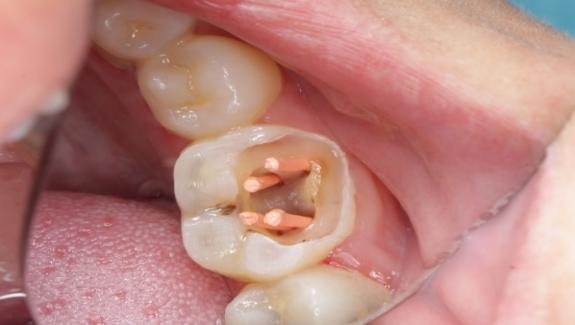

(三)根管治療

如果齲齒已經(jīng)侵犯到牙髓,引起牙髓炎或根尖周炎,就需要進(jìn)行根管治療。根管治療是去除感染的牙髓組織,對根管進(jìn)行消毒和充填,最后再進(jìn)行牙冠修復(fù)。

例如,對于深度齲齒導(dǎo)致的牙髓炎,根管治療是保留患牙的有效方法。